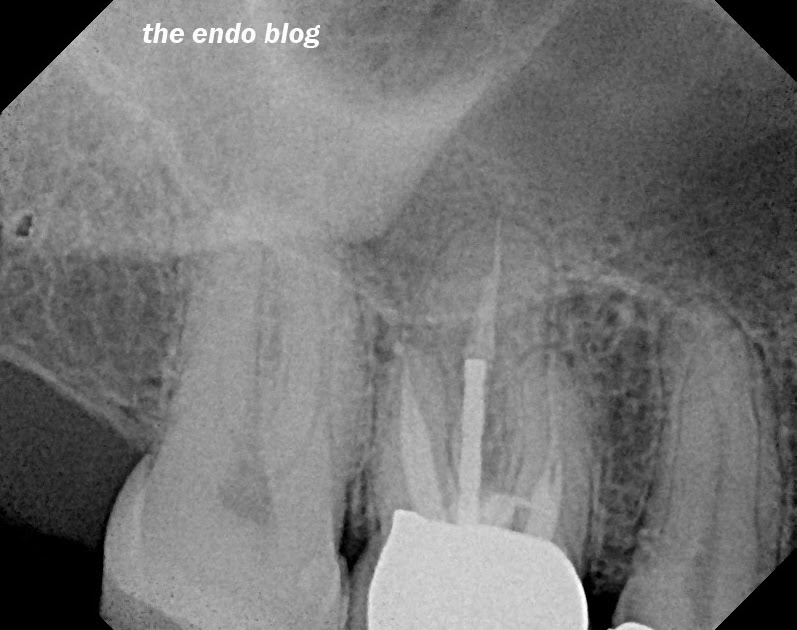

From www.theendoblog.com

The Endo Blog Microscopes & Management of Root Canal Perforation What Is A Perforated Root Canal Once a perforation is properly diagnosed, located, and. Perforation of the pulp chamber or root walls during instrumentation of root canals exposes the supporting tissues of the tooth to bacterial contamination and often leads. A tooth perforation is a pathologic or iatrogenic communication between the root canal space and the periodontal apparatus. Root perforation results in the communication between root. What Is A Perforated Root Canal.